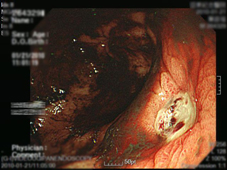

內視鏡下胃潰瘍出血